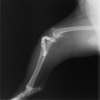

術後写真

手術前後のTPA(脛骨高平部の角度)を測定しています。

約29°から約10°へ矯正されています。